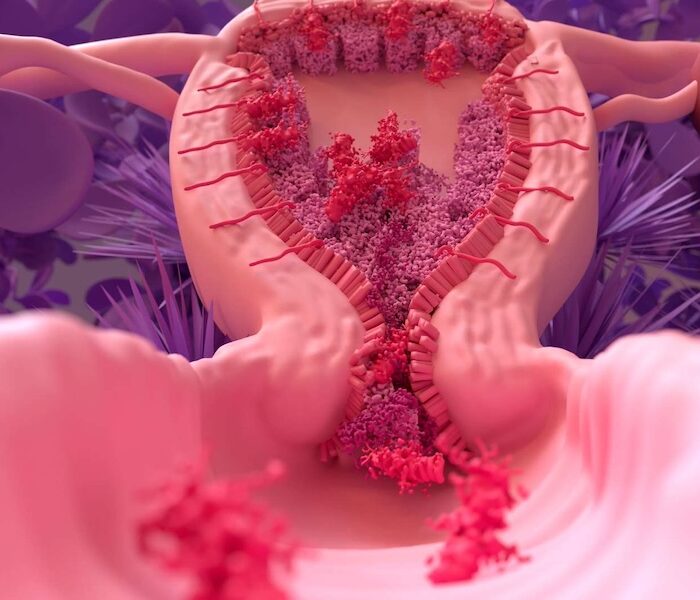

- Chequeos de Papanicolau y colposcopía para detección precoz de cáncer de cuello uterino.

- Patologías ginecológicas frecuentes como quistes ováricos, endometriosis y miomas.